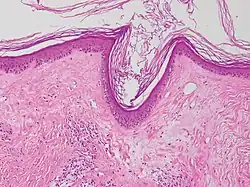

Vacuolar interface dermatitis (VAC, also known as liquefaction degeneration, vacuolar alteration or hydropic degeneration) is a dermatitis with vacuolization at the dermoepidermal junction, with lymphocytic inflammation at the epidermis and dermis.[1]

| Generally/Not otherwise specified | Typical findings, called "":[2]